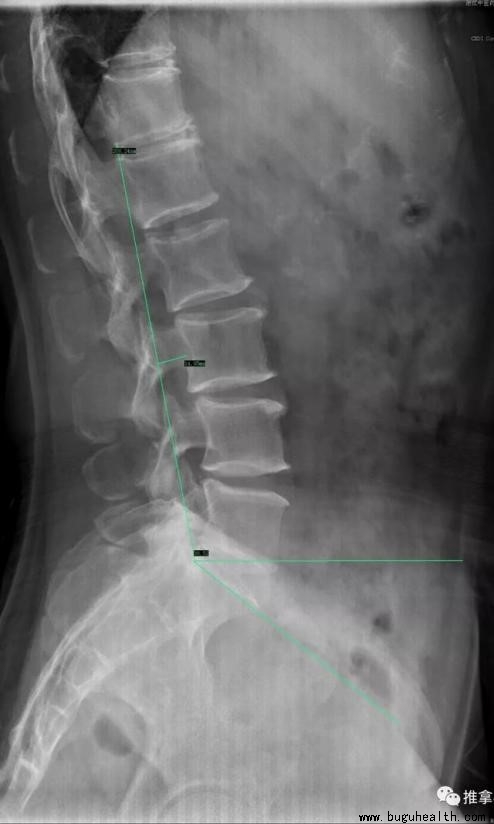

腰椎:Seze 法,即在 Χ 线侧位片上自T12椎体后下角至 S1后上角做一连线,腰椎各椎体后缘的弧形连线与此线形成一弓,弓顶点正常在 L3,弓顶点与弦垂线距离正常为18~22mm,大于22mm则为腰曲过大。

骶椎在人类发育过程中会相互融合,形成一个坚固的骶骨,组成骨盆的后壁,故而主要通过对腰骶角的观察测量来分析骶骨的位置关系。

腰骶角:Ferguson测量法,即在Χ线侧位片上以骶骨上缘的切线与水平线做一夹角,即为腰骶角,研究表明正常值约为33.7°~49.1°,也就是如果腰骶角大于49.1°就可以说是腰骶角过大。